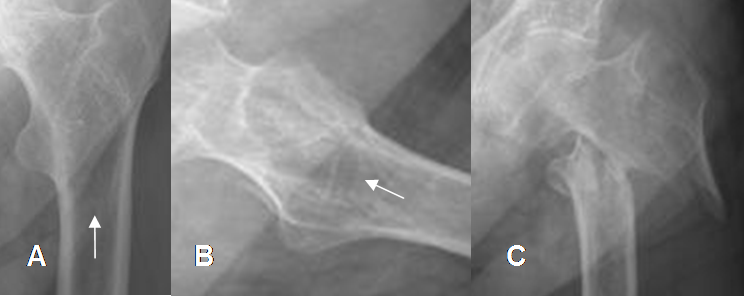

Fig 134. Quiste óseo simple.

Mayor frecuencia entre los 5 y 15 años. Predominio en la parte proximal de los huesos largos.

Lesión metafisiaria, de ubicación excéntrica.

Fig 135. Quiste óseo simple.

A: Rx AP, B: TAC reconstrucción sagital y C: TAC axial. Imagen ovalada y de bordes escleróticos en el escafoides, por quiste simple.

Fig 136. Quiste óseo simple.

A: TAC reconstrucción sagital, B y C: TAC axial. Imagen central de bordes parcialmente definidos, que reemplaza le medular del tercio proximal del fémur y corresponde a quiste simple.